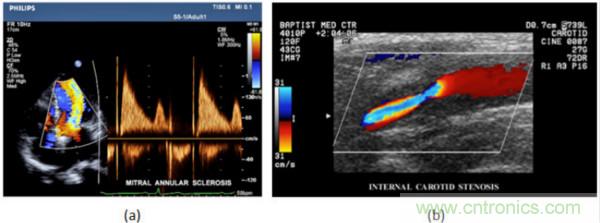

在CW和PW多普勒模式中,流信息是從一個聚焦聲束中獲得的,類似于A模式成像。在20世紀(jì)80年代,研究人員基于彩色多普勒技術(shù)完成了血流分布的二維信息可視化。彩色多普勒處理也是基于B模式/PW模式信號路徑。從感興趣區(qū)域收集多幀RF數(shù)據(jù)。由于感興趣區(qū)域中的血液流動導(dǎo)致圖像幀之間存在數(shù)據(jù)差異。相域中的自相關(guān)和時域中的互相關(guān)兩種算法可從RF數(shù)據(jù)中提取數(shù)據(jù)方差(即血流速度和方向信息):。根據(jù)預(yù)定義的顏色漸變條相應(yīng)地映射包括速度和方向的血流信息。通常,藍(lán)色和紅色代碼分別識別朝向和遠(yuǎn)離換能器移動的血流。當(dāng)流速增加時使用更亮的顏色,反之亦然。顏色映射的2D分布始終疊加在B模式圖像上,以實(shí)時同時顯示個體解剖結(jié)構(gòu)和血流。它對于診斷心血管疾病,如血管閉塞和心臟瓣膜反流,極其有用。典型的彩色多普勒圖像如下圖所示,(b)顯示頸動脈狹窄引起的血流流速變化。

圖7.彩色多普勒成像:(a)以彩色多普勒和CW模式獲得的圖像(由Philips提供); (b)顯示頸動脈狹窄的彩色多普勒(由GE提供)